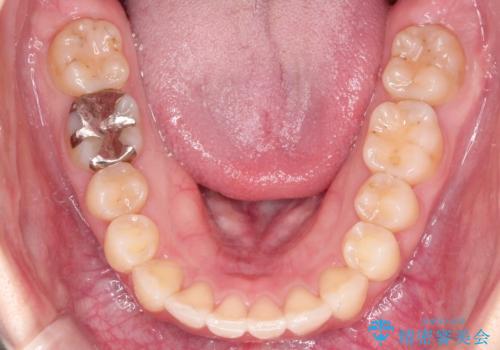

【インビザライン】前歯が出てるのを治したい

- 前歯の凸凹と前突を主訴に来院されました。

インビザラインにて治療をおこない、歯並びを改善することができました。